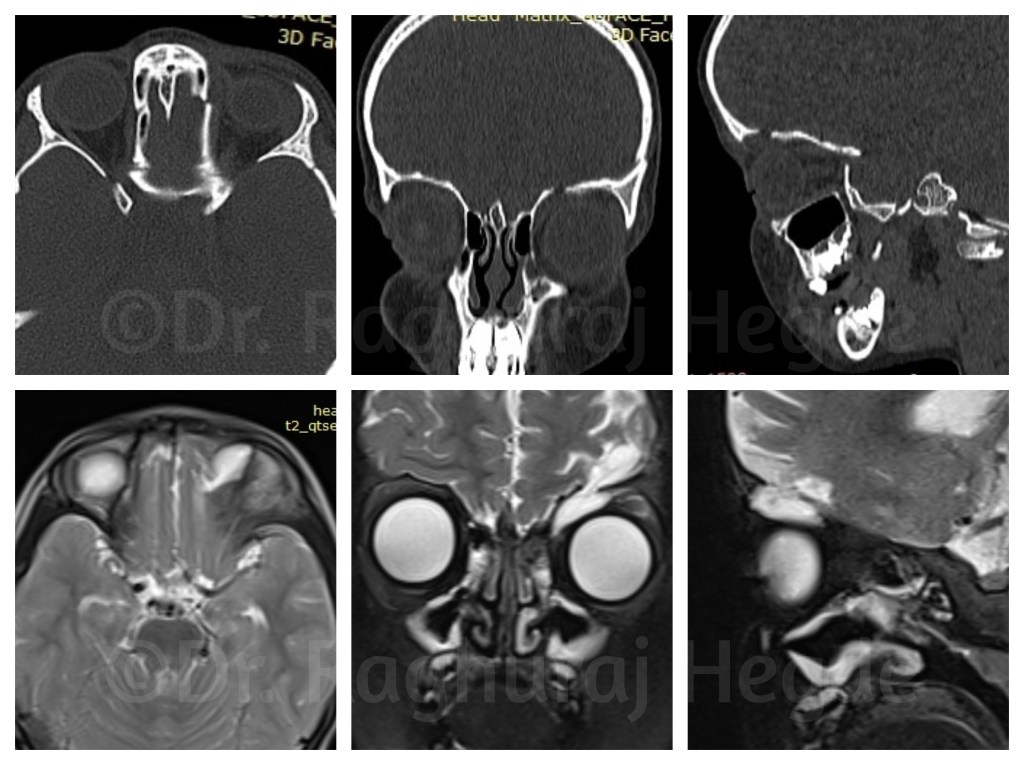

Her CT Scan showed why it was so.

She had crack in her skull starting from her Left ethmoid sinus passing through her left orbit superiorly into the frontal bone- a huge ugly crack. There was a direct tract from the sinuses to the subcutaneous space. Whenever she cried the increased sinus pressure would force air into the orbit and then into the skin which would be seen as a swelling. It was the cause of subcutaneous emphysema. The coronal, saggital and axial cuts confirmed the course of the orbito-frontal- cranial fracture line.

However on examination something didn’t make sense- the hypoglobus- pushing the left eye down. I carefully scouring the CT scan DICOM data in my computer from which I couldn’t pin-point a reason despite a left orbital roof defect.

To rule out a CSF leak, I ordered an MRI scan with contrast. On the scans it was imediately made clear that there was a meningoencephalocele into the left orbit. There was possibly a dural tear and CSF leak from that tear itself.

Correlating the CT scans with the MRI showed that the meningocele was through the left orbital roof defect.